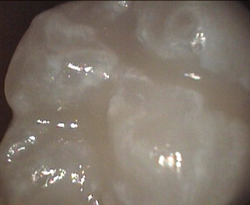

Unusual prevalent but superficial groove pattern on permenant molar after Sealed